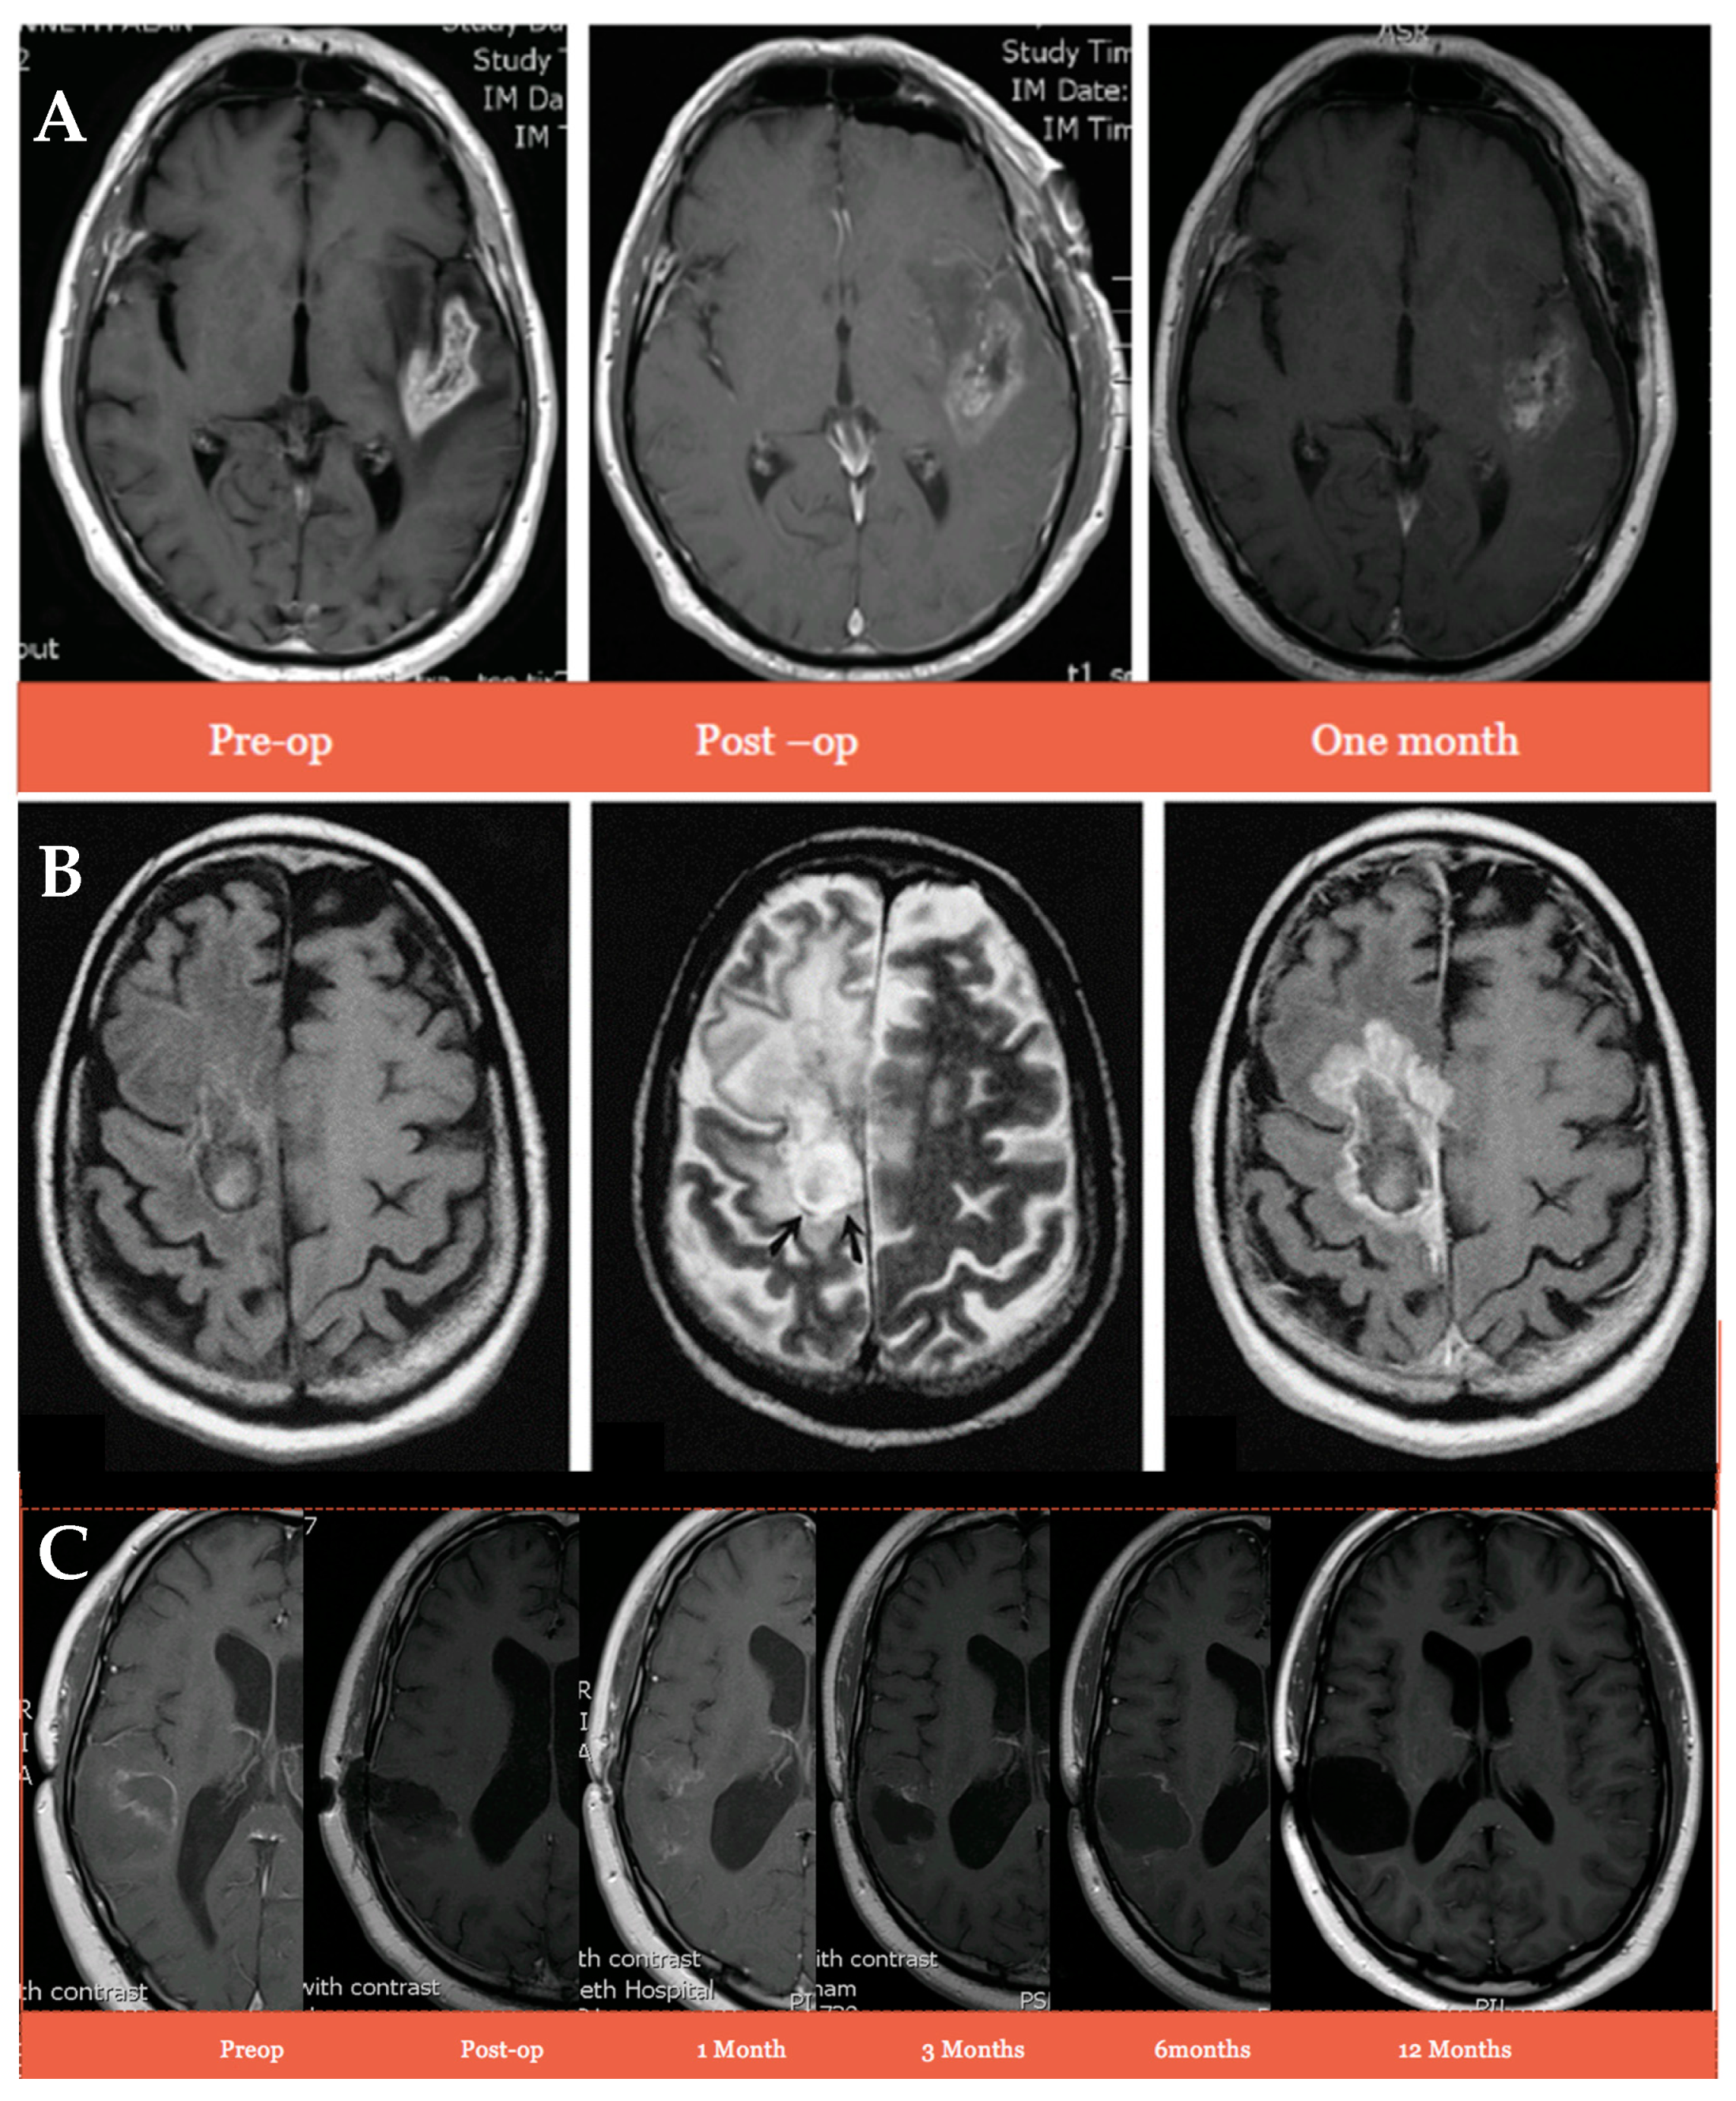

3.2. Steroid Use and Swelling in Recurrent GBM Patients after Intraparenchymal Administration of IRN Directly into the Resection Margin Compared to Patients Administered the Gliadel Wafer

3.4. The Impact of Intraparenchymal Administration of IRN Directly into the Resection Margin on the Survival of Recurrent GBM Patients